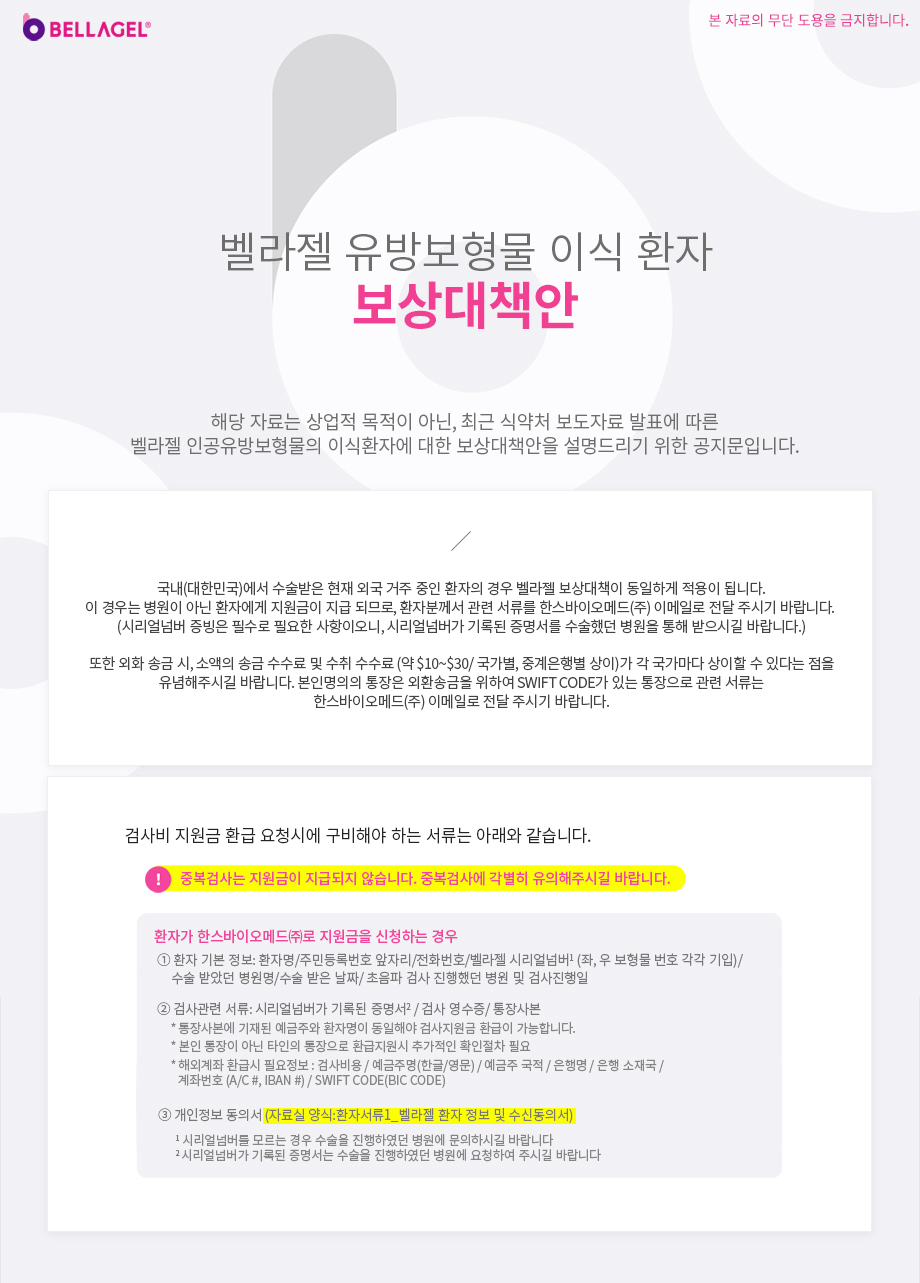

보상대책안

벨라젤 외국인 환자에 대한 보상지원